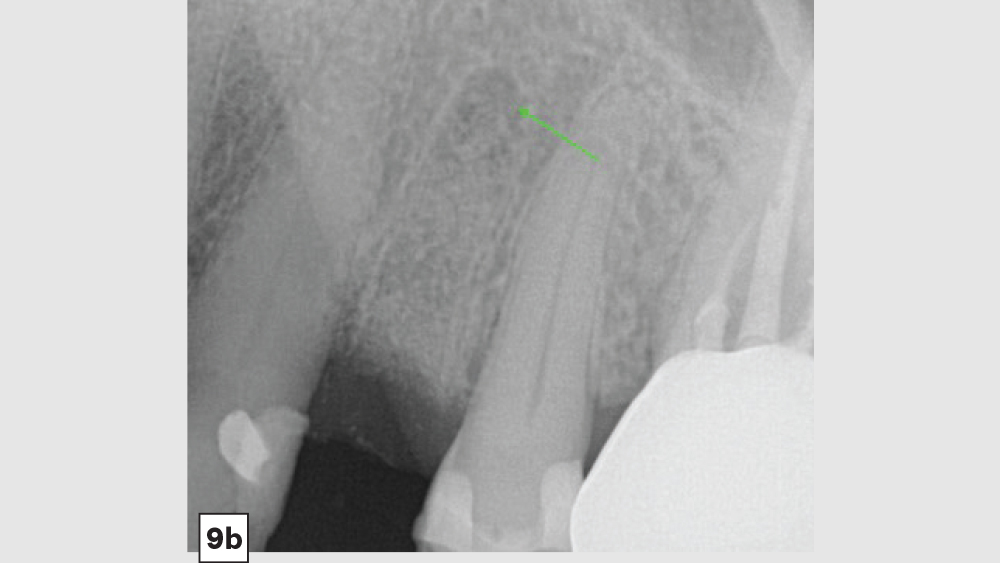

The most common complication from socket grafting techniques is inadequate bone graft fill (Figs. 9a, 9b). Care should be exercised to add bone in small increments, especially to ensure that bone is placed in the apical one-third of the socket. A bone packer should be used with good condensation to avoid air spaces. Additional complications include overfilling of the graft material (Fig. 10). Bone graft material should be placed at the level of the bony crest to allow space for the membrane. If excess bone graft material is condensed above the bone crest, delayed healing will occur.

Figure 9b

Figures 9a, 9b: Inadequate socket grafting with large voids in apical one-third (9a), inadequate bone fill with resultant air space (9b).